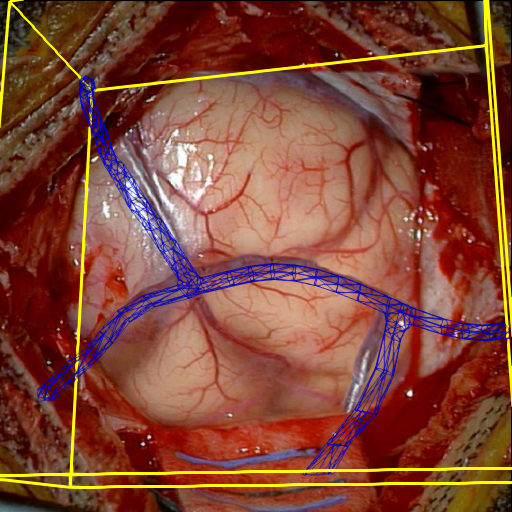

Fig. 5 shows our results as Augmented Reality views with bounding boxes and overlaid meshes. Our method produced visually consistent alignments for all 6 clinical cases without the need for initial registration. Because our current method does not account for brain-shift deformation, our method produced some misalignment errors. However, in all cases, our predictions are similar to the ground truth.